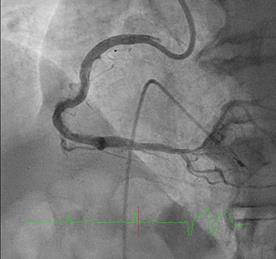

Can thiệp ngã ba động mạch liên thất trước và nhánh chéo 1 với hai stent có bọc thuốc bằng kĩ thuật cullote. Tiếp tục can thiệp động mạch vành phải với ống thông can thiệp (guiding catheter) (Cordis JR4 cm 6Fr) và dây dẫn (Asahi Sion 0.014”). Nong tổn thương bằng bóng 3.5 x 15mm (Neich Sapphire), bóng 4.0 x 12 (NC Quantum Apex), bóng cắt 3.5 x 15 (Cutting balloon, Angiosculpt) không làm vỡ được mảng vữa xơ. Quyết định dùng hệ thống khoan cắt mảng vữa xơ với dây dẫn mềm (Boston Scientific Rotablator Rotalink Plus) và mũi khoan (burr) 1.5mm. Tuy nhiên vì kích thước động mạch quá lớn nên mũi khoan đi qua tổn thương mà không chạm vào mảng vữa xơ được. Chuyển sang mũi khoan có đường kính lớn hơn 2.15mm với tốc độ khoan 150000 vòng /phút. Khi mũi khoa đi qua được 1/3 tổn thương thì không thể di chuyển được tiếp. Nhận định tại thời điểm đó là mũi khoan bị kẹt trong tổn thương tại đoạn giữa của động mạch vành phải. Ngay lập tức các bác sỹ có kinh nghiệm can thiệp trong bệnh viện được mời đến phòng can thiệp đồng thời thông báo cho các phẫu thuật viên tim mạch chuẩn bị trong trường hợp cần thiết. Bệnh nhân có biểu hiện đau tức ngực trái, tuy nhiên mạch và huyết áp tương đối ổn định, điện tim không thay đổi. Dòng chảy trong động mạch vành còn duy trì nhưng chậm TIMI 2. Sau khi hội ý, hướng xử trí đầu tiên là dùng dây dẫn cứng Conquest Pro (Asahi) để đi qua tổn thương nhưng không thành công. Sau đó chúng tôi quyết định cắt đoạn đầu của hệ thống nối mũi khoan, đưa ống thông heartrail (Terumo) sát vào mũi khoan nhằm thay đổi tư thế và cố định mũi khoan vào dây dẫn để đưa ra ngoài. Cuối cùng mũi khoan được đưa ra ngoài thành công. Tổn thương tiếp tục được nong bằng bóng cắt và bóng áp lực cao và đặt được giá đỡ kim loại (stent) bọc thuốc 4.0 x 26mm. Kết quả là động mạch vành được mở rộng hoàn toàn, bệnh nhân không còn đau ngực, huyết động ổn định.

Hình 1: A- hình ảnh động mạch vành trước can thiệp; B – dùng bóng cắt (cutting balloon) không phá vỡ được cấu trúc mảng vữa xơ; C – mũi khoan 1.5 không chạm vào được mảng vữa xơ vôi hóa; D – mũi khoan 2.15 bị tắc tại vị trí hẹp.